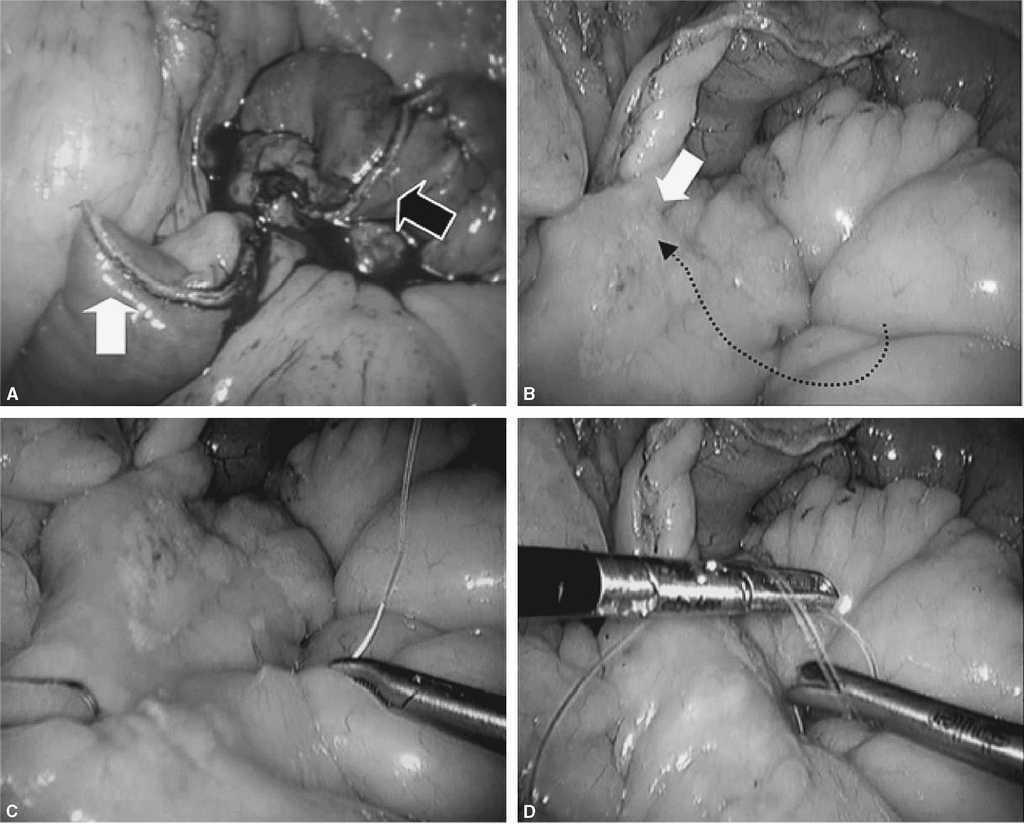

Fig. 3. A: tras la sección del intestino delgado unos 25 cm del ángulo de Treitz, podremos identificar el asa biliopancreática (flecha negra) y el asa de Roux (flecha blanca). B: la técnica del cierre mesentérico comienza plicando el mesenterio del asa en Y de Roux en dirección al punto de sección mesentérico (flecha blanca). C: para plicar la base del asa de Y de Roux es suficiente con pasar la aguja de forma superficial 2-3 veces hasta que se llega al punto de sección. D: una vez plicado el mesenterio, se anuda la sutura y no se corta. Esta sutura servirá posteriormente para cerrar el defecto del asa sobre el mesocolon (sutura 1 de la fig. 5D).

Fig. 4. A: ahora centraremos la atención en cerrar el defecto mesentérico de la yeyuno-yeyunostomía como se indica en la figura. Es importante coger con los primeros puntos de la sutura ambas asas (biliopancreática, flecha blanca) para evitar el acodamiento como causa de obstrucción (antiobstruction stitch). B: se puede observar en la flecha blanca cómo se ha rectificado la anastomosis enteroentérica para evitar acodamientos. C: posteriormente, a medida que se avanza la aguja, sólo se cogerá superficialmente el mesenterio. D: al final del cierre nos encontraremos la cola de la sutura anterior de la plicatura del asa Y de Roux con la que anudaremos conjuntamente. Es importante no cortar la aguja que nos servirá para continuar el cierre.

Fig. 5. A: en este momento tendremos 2 suturas con 2 agujas que parten del mismo punto. Una de las 2 suturas pasará por debajo del asa de Roux en su punto más craneal (flecha blanca) y la otra se quedará en el mismo sitio (lado izquierdo del asa de Roux). La flecha negra indica la yeyuno-yeyunostomía. B: se avanza el asa de Roux al orificio creado en el mesocolon con un grasper atraumático. C: identificamos fácilmente la sutura que pasamos previamente por debajo del asa Y de Roux. D: se observa las 2 suturas.

Fig. 6. El objetivo ahora es seguir con la sutura continua por ambos lados del asa Y de Roux cerrando el espacio de Petersen y ojal de mesocolon transverso haciendo una corbata. A: cómo se hace con la sutura 1 el cierre del meso en el lado izquierdo. B: es importante para este propósito coger la serosa intestinal y tejido graso del meso. C: en el cuadrado blanco se aprecia que la sutura avanza y coge serosa intestinal. D: una vez llegado a la mitad se deja la sutura y avanzaremos la sutura 2 desde el otro lado hacia la sutura 1.

Fig. 7. A: identificamos la sutura 2 y preparamos el campo para comenzar la hemicorona desde el lado derecho al izquierdo hasta encontrarnos con la sutura 1. B: se realiza plicatura del meso con una sola pasada de la aguja y se asciende. Aquí estamos cerrando el espacio de Petersen desde el lado derecho del asa Y de Roux. C: se avanza hasta encontrar la sutura 1 en el punto medio, cogiendo serosa intestinal y grasa del mesocolon (cuadro blanco). D: cuando se realiza tracción del hilo (Ethibond®), se plica el meso cerrando el espacio de Petersen.

Fig. 8. A: como se indica en la figura, las 2 suturas se han encontrado en la línea media del defecto mesocólico. B: es el momento de anudar ambas suturas. C: es importante, como se indica en el cuadro blanco, no ejercer mucha tensión en el nudo de esta sutura porque se puede producir una obstrucción iatrogénica comprimiendo la salida del asa de Roux (hay que tener en cuenta que toda la sutura es continua y hay que ejercer la tensión apropiada para cerrar el espacio entre el orificio del mesocolon transverso y el asa Y de Roux). D: se ha anudado ambas suturas y se comprueba que no se ha afectado la salida del asa alimentaria en el mesocolon.